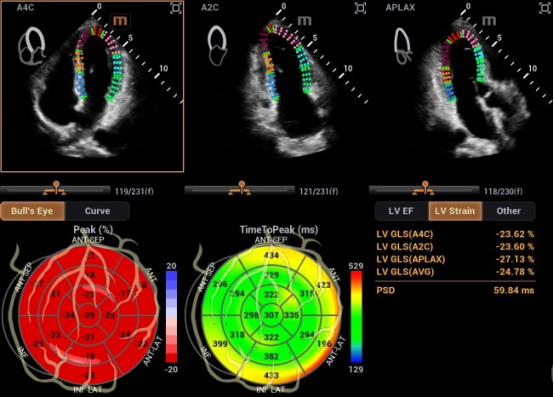

在研发中,迈瑞研发团队另辟蹊径,推出了自动左心室应变评估 Auto Strain LV 。该功能不再依赖心电信号作为“时间坐标”,而是让AI直接识别心脏机械运动的关键节点——当二尖瓣关闭、主动脉瓣开放,这些瓣膜运动的瞬间,就是心脏收缩与舒张的自然锚点。

自动左心室应变评估 Auto Strain LV(非心电触发)

迈瑞也在与尹立雪教授团队牵头的合作项目中,挖掘出自动左心室应变评估 Auto Strain LV 更多的临床应用价值,成功让心肌应变检测技术摆脱“心电图(ECG)”的束缚。尹教授表示:“基于人工智能的图像技术,现在已实现无需同步心电图的自动心肌应变分析。该技术操作便捷,检测结果与传统方法高度一致,且能早于传统指标识别心肌功能异常,为疾病早期干预提供关键支撑。”

摆脱心电图束缚后的心肌应变测量技术最明显的变化就是“快”。应用新技术后,临床检查的操作时间从10分钟缩短至3分钟以内,显著地降低了技术门槛,让床旁、急诊、大规模筛查成为可能。

同时,这项技术的数据直接源于机械运动的时相判定,没有电信号干扰与延迟误差,更真实地反映心脏“做了什么”。有效避免了心律失常、起搏器植入、幼儿及急诊术中等场景下,心电信号出现缺失、干扰的影响。